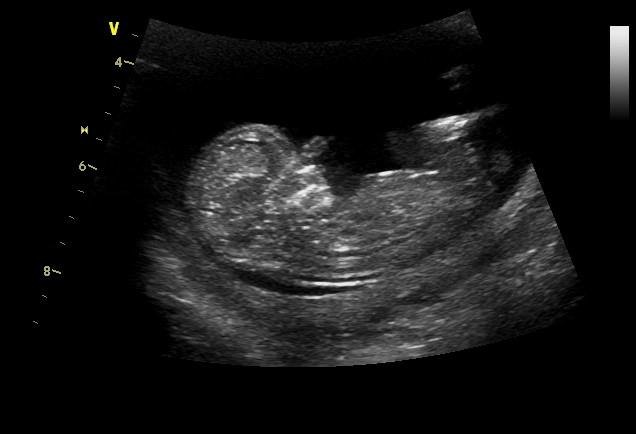

Majinko, to je krása! :) i ostatní fotečky! Dávám svoji před 2 týdny: 6,14cm